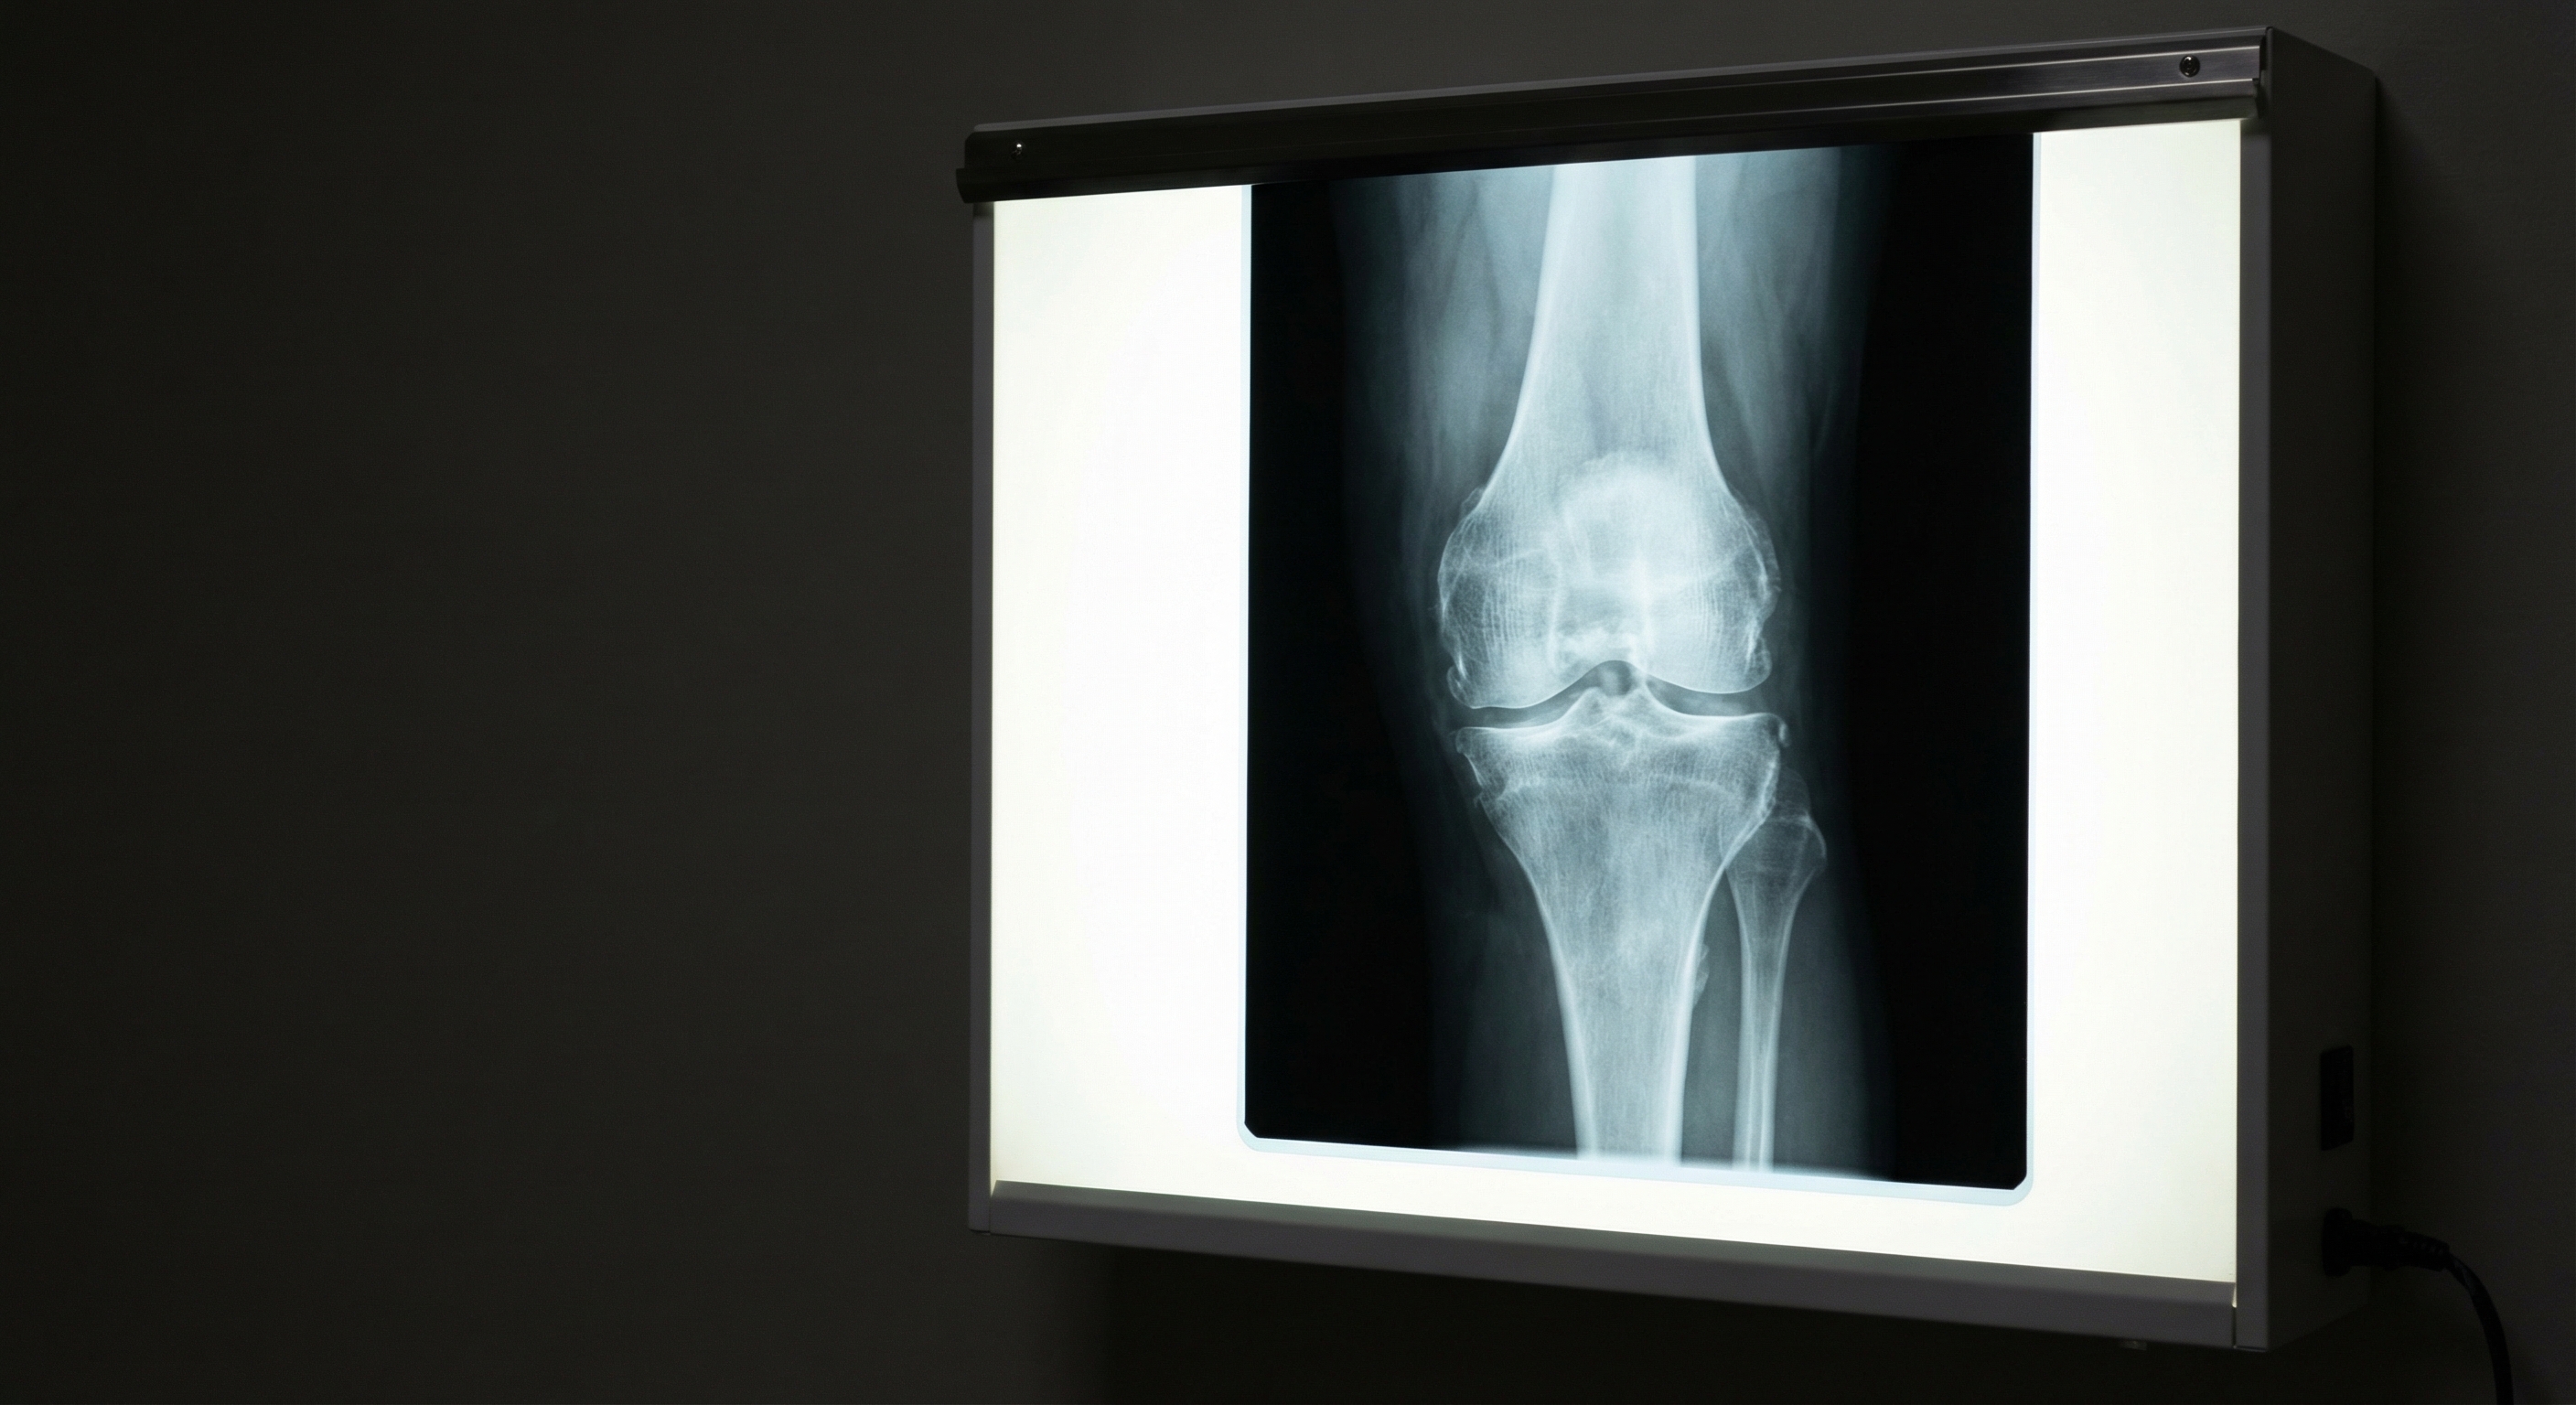

Osteoarthritis represents the most common form of arthritis, affecting millions of people worldwide. This degenerative condition develops when the protective cartilage that cushions the ends of bones wears down over time, leading to bone-on-bone contact and resulting pain, stiffness, and reduced mobility. Osteoarthritis commonly affects weight-bearing joints such as the knees, hips, and spine, but can also impact the hands and other joints throughout the body. The progression of osteoarthritis is typically gradual, with symptoms worsening over many years.

Risk factors for osteoarthritis include advancing age, joint injury, repetitive stress on joints, obesity, and genetic predisposition. While there is no cure for osteoarthritis, various treatment approaches can effectively manage symptoms and maintain joint function. Treatment typically begins with conservative measures such as weight management, exercise, physical therapy, and pain medications, progressing to more advanced interventions as needed. Understanding these risk factors can help individuals take preventive measures and seek early intervention when symptoms first appear.

When conservative treatments fail to provide adequate relief, surgical options may be considered. Joint replacement surgery, particularly for knees and hips, can dramatically improve function and reduce pain in advanced arthritis cases. Other surgical procedures include joint fusion, tendon repair, and minimally invasive arthroscopic surgeries to remove debris or repair damaged tissue.